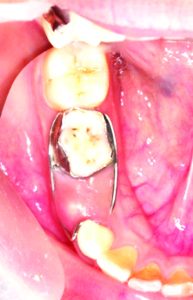

Consider the case of a 5-year-old patient whose lower second milk molar was affected by a condition known as Molar Hypomineralisation. The tooth was filled to address the decay.

The Positive Outcome: Two years later, the permanent molar erupted in its intended position behind the same. This early intervention prevented the decay from impacting the alignment of the permanent teeth. If the milk tooth had not been treated, the space left by the decay could have caused the permanent molar to erupt improperly, potentially leading to future orthodontic issues and the need for braces.